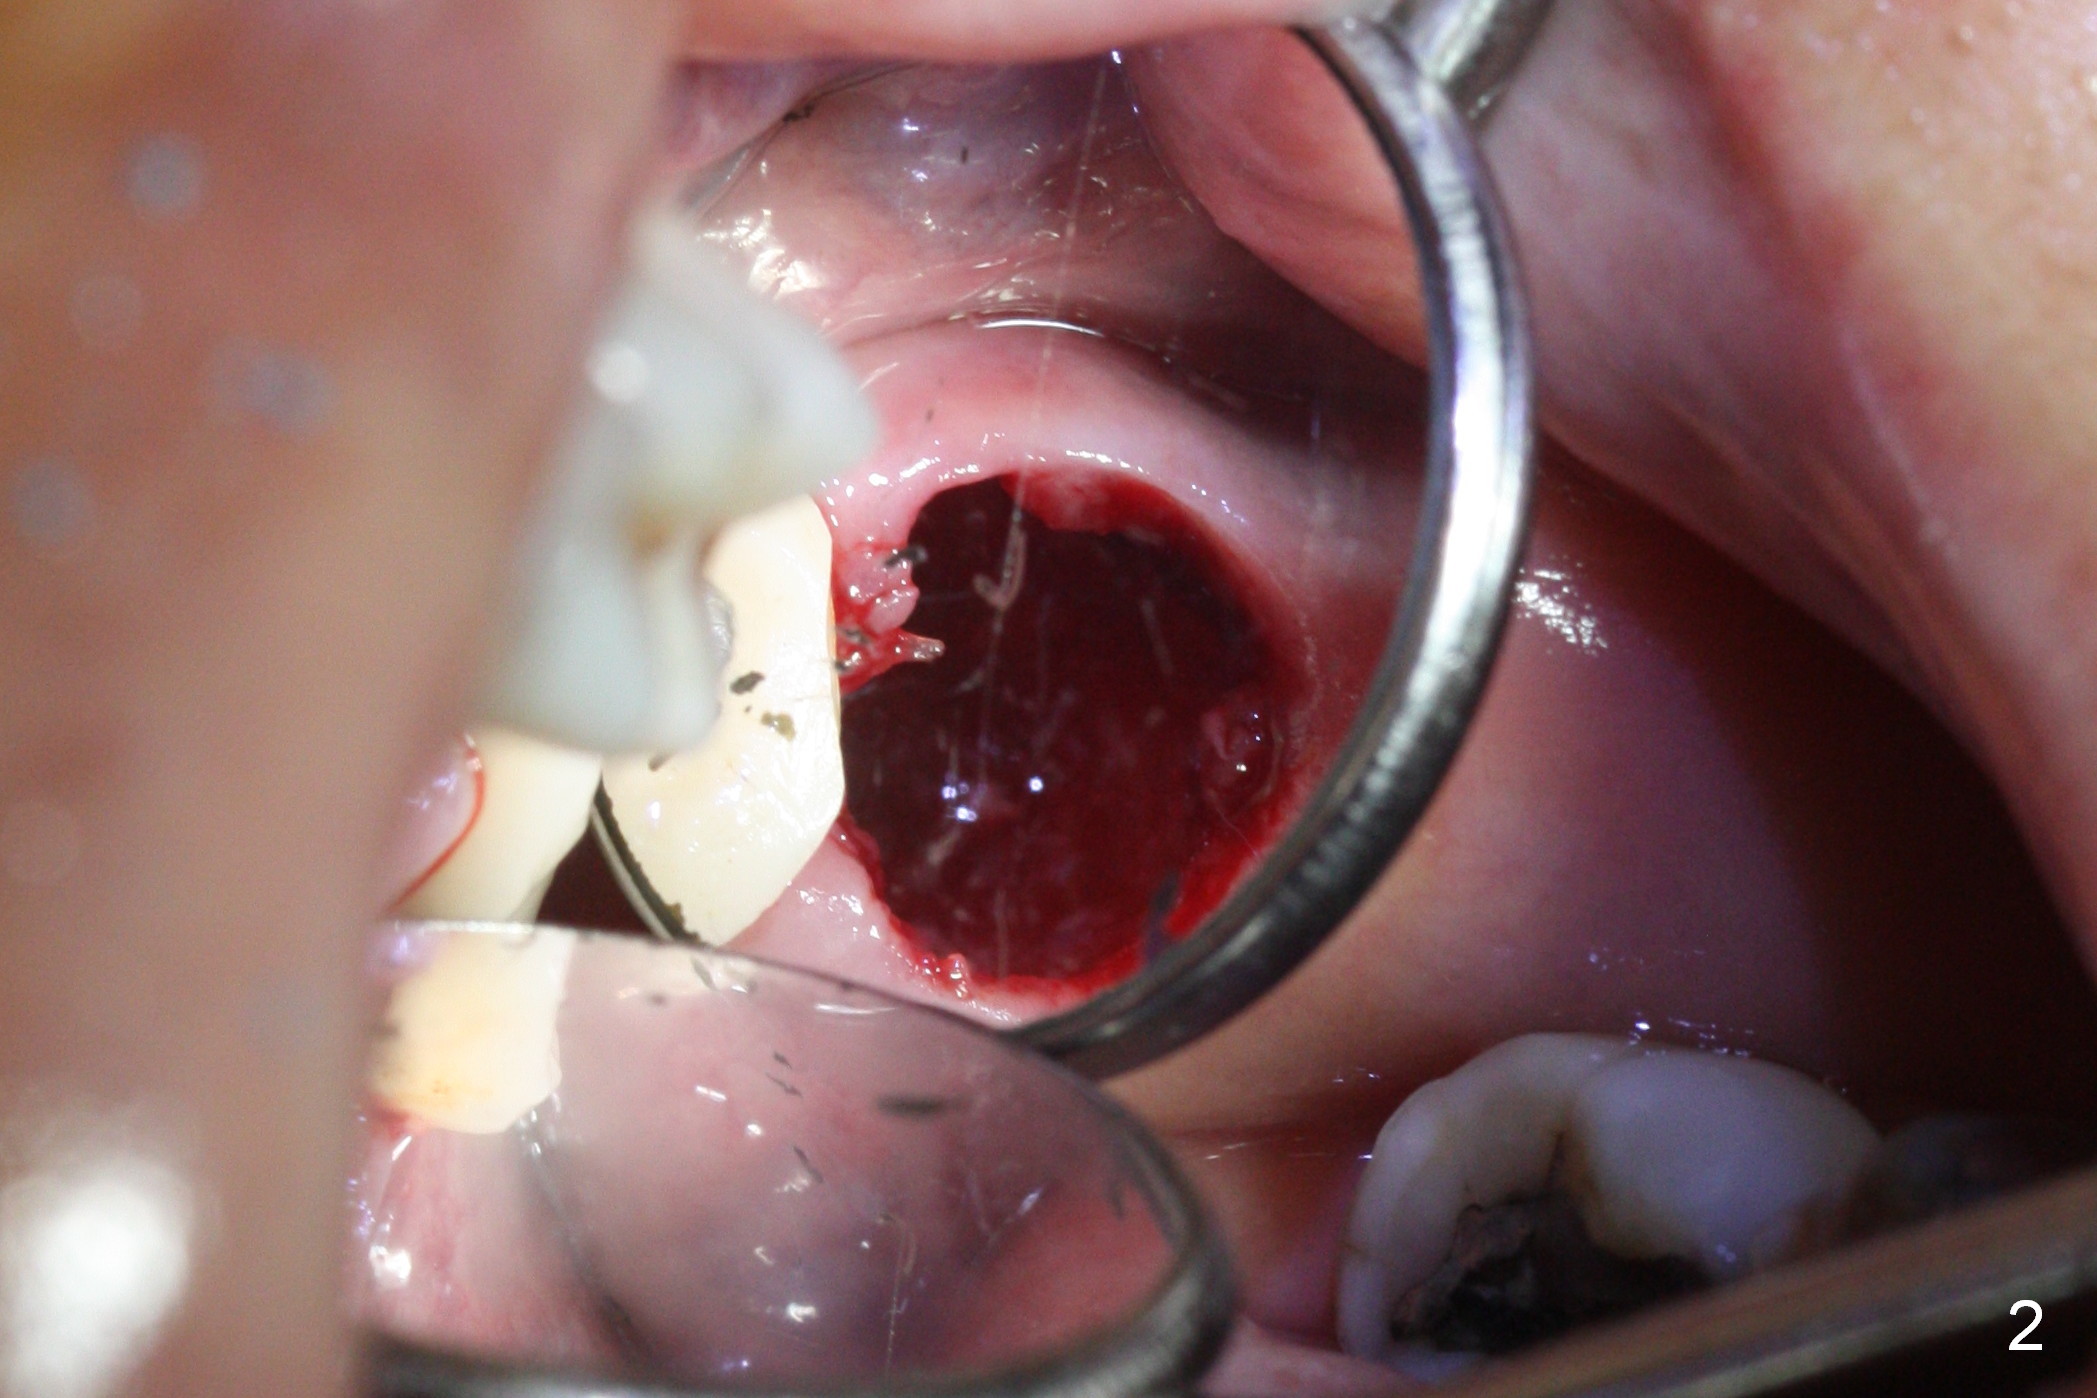

There is abundant subgingival calculus on the surfaces of the extracted tooth at #14 (Fig.1: P: palatal; MB: mesiobuccal), corresponding to the large empty socket (Fig.2 without septal bone, the buccal plate being low). Osteotomy is established palatally with Magic Expander (ME) 3.0 mm for ~ 3 mm deep (Fig.3,4) with minimal stability so that it moves during X-ray taking (Fig.4). Since the bone is dense, Magic drill 4.3 mm is used after application of ME 3.8 and 4.3 mm to complete sinus lift (Fig.5 (panoramic X-ray)). A 5x11 mm implant is placed with ~ 30 Ncm, followed by insertion of 6.5x4(3) mm Hexa abutment, bone graft and collagen membrane (Fig.6). The latter is kept in placed with an immediate provisional with clearance from the opposing dentition (Fig.7 *). Between the 1st and 3rd weeks postop, the buccal gingiva recedes with loss of bone graft (Fig.8 <) and implant thread exposure (Fig.9 * (A: abutment)). After inducing hemorrhage, allograft is placed (Fig.10 >), followed by collagen dressing (Fig.11 >). The wound closes by adding new acrylic (Fig.12 *). Thirteen days later, food is trapped in the buccal gap (Fig.13 ^). It appears that the provisional does not help wound healing. The provisional and abutment are removed; incorporating bone graft (Fig.14 *) and the implant are exposed. After placing collagen plug against the bone graft and implant, the wound is closed by periodontal dressing.